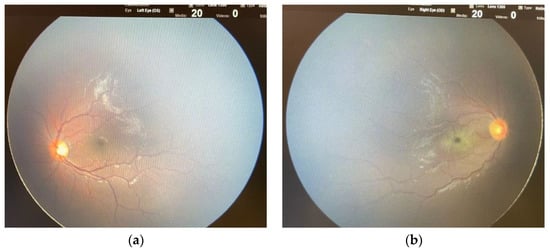

Three patients were diagnosed with AIS during the COVID-19. A 12-year-old boy had a left cerebellar stroke (Figure 2) due to PICA occlusion with a complete clinical recovery but partial radiological improvement. The second was a 15-year-old boy with consciousness impairment and bilateral thalamic ischemic lesions. Despite a clinical improvement, a one-month control brain MRI showed a new cortex ischemic injury. At discharge, his neurological impairments improved with persistent confusion episodes. The third was a six-year-old girl who presented a right central retinal artery occlusion (CRAO) together with an idiopathic contralateral optic neuropathy (Figure 3). Neuroimaging (brain CT, MRI, and angiography) was normal. She completely lost her right eye function, but she recovered her fingers counting on the left.

Figure 3.

Fundus examination in a six-year-old girl with central retinal artery occlusion (CRAO) during COVID-19 (with kind concession of P. Fortunato MD). (a) Normal fundus in the left eye. (b) In the right eye characteristic funduscopic findings of CRAO: retinal whitening, cherry red spot in the fovea and filiform retinal arteries.

Although uncommon, stroke is a possible complication of COVID-19 and MIS-C, even in the pediatric age, and several cases are reported in the literature [16,17,26,27,47]. In this series, three patients experienced an ischemic stroke during the COVID-19 course, and one of them specifically presented a retinal infarction due to CRAO. [48]. To the best of our knowledge, our case is the first report of CRAO in children with SARS-CoV-2 infection. Nevertheless, several cases have been reported in adults, and a combined central retinal artery and vein occlusion has been described in a 20-year-old Indian [49,50,51]. In addition, it is known that the SARS-CoV-2 infection prothrombotic effect may also involve the ocular district [52]. The girl in our study with CRAO experienced a contralateral idiopathic optic neuropathy. Optic neuritis has been reported during COVID-19, as well as other viral infections; however, in our case, brain and orbits MRI excluded optic nerve signal alterations [16,27].